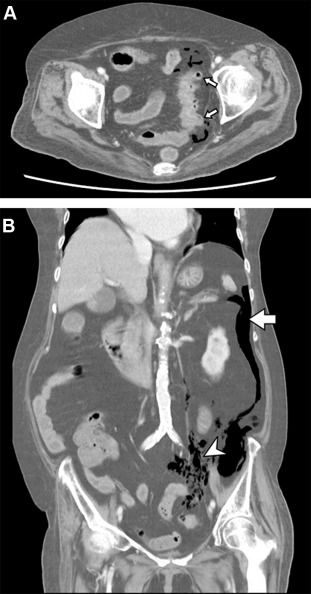

Pathology report shows acute diverticulitis with perforation.